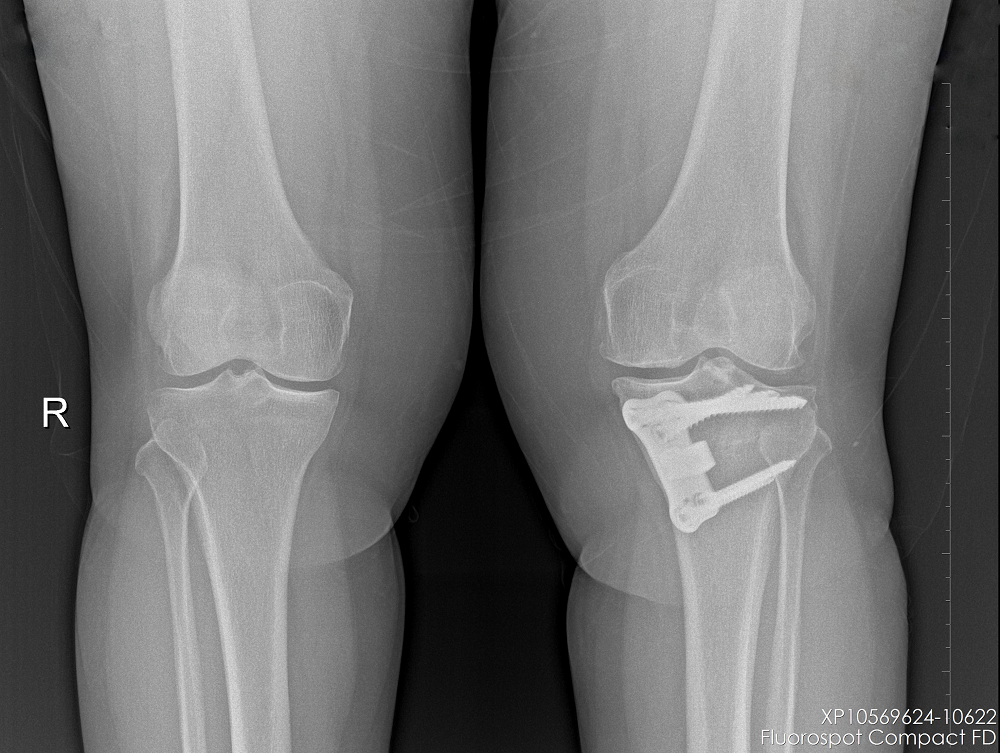

Gonartrozu olan hastanın ameliyat öncesi ve YTO yapıldıktan sonraki grafileri